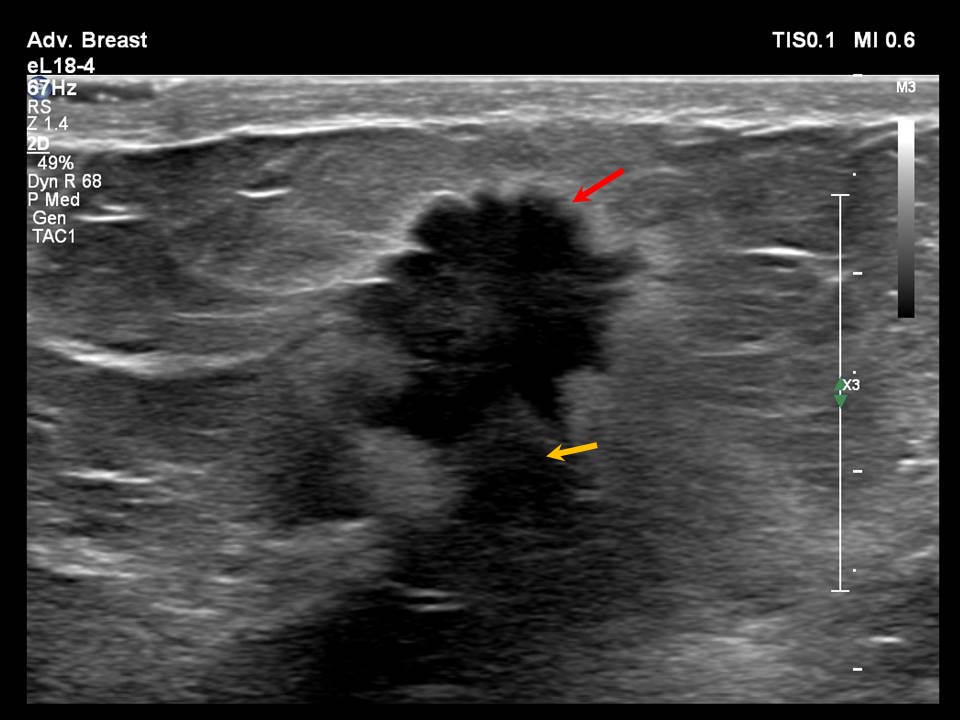

US (A) Spiculated breast mass with strong Posterior Acoustic Shadowing Spiculated Margins It has been our experience that. Spiculated margins are seen in malignant masses. The classic description of a breast cancer is a mass with an irregular shape and spiculated margin (fig. Click on the pictures to. They describe the extent and possible infiltration of the mass into the surrounding breast parenchyma. Spiculated masses are defined as masses with lines radiating. Spiculated Margins.

From www.mdpi.com